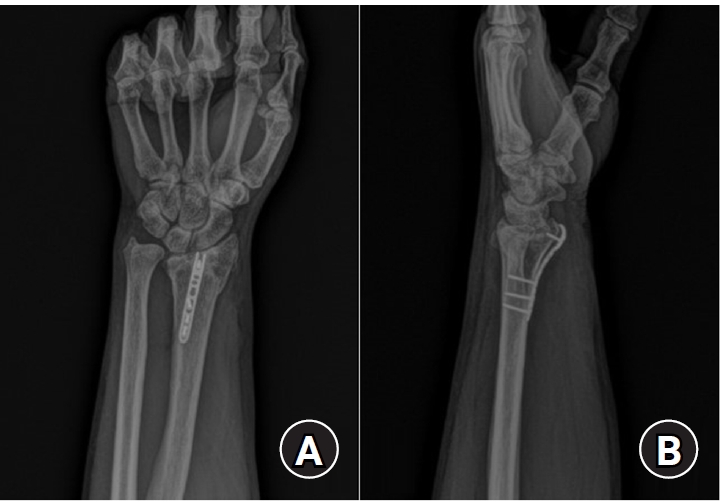

Fig. 2.

Postoperative radiographs (A) anteroposterior and (B) lateral: a 2.0 mm locking compression plate distal ulnar hook plate (Synthes) used for fixation in a distal radius fracture with a volar lunate facet fragment.

jmt-2025-00241f2.jpg